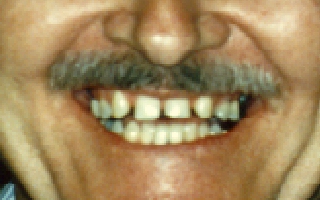

This patient is congenitally

missing his lateral incisors, that is, he was born without the two teeth

that are normally located next to the front teeth. Through the use of

orthodontic appliances, we brought the canines (eye teeth) back and

closed the gap between the front teeth to make enough room for

artificial teeth. Then, bridgework was prepared and cemented in

permanently. |